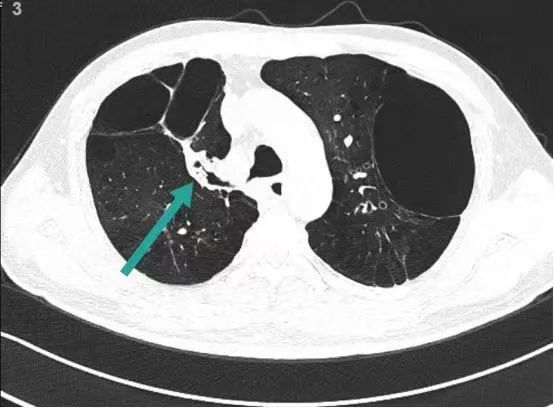

48岁的王先生因自述“反复咳嗽咳痰、气喘二十余年,加重一周”,于2月14日慕名到院治疗。过去二十年间,他因严重气喘无法远行,日常步行百米即需停歇,活动范围仅限小区花园。CT检查显示其双肺上叶存在巨大肺大泡,严重挤压正常肺组织,导致肺功能急剧下降。

2月26日,呼吸与危重症医学科行政主任刘祁汨采用肺叶通气功能检测系统,精准评估患者右肺上叶及左肺上叶支气管通气功能。为兼顾疗效与经济性,团队创新设计“分步疗法”:首阶段实施右肺上叶前段支气管活瓣置入,待靶区肺大泡充分萎陷后取出活瓣,再根据疗效评估选择适宜区域进行二次置入,最大化减少手术费用。

术后第二天评估显示,王先生平地行走距离提升至300米,自觉气喘症状显著缓解。肺功能检测数据更直观:FVC(用力肺活量)提升0.14L,FEV1(第一秒用力呼气容积)改善0.08L。数字背后,是呼吸自由的真实回归。